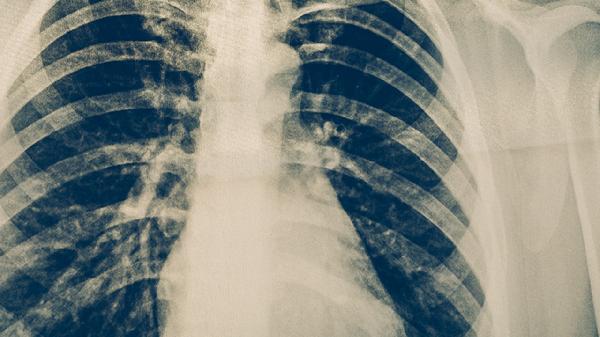

醫(yī)務人員、矽肺患者、免疫功能低下者等應每年進行胸部X線檢查。結核菌素試驗強陽性者需接受胸部CT排查,必要時進行6-9個月的異煙肼預防性治療。學校、養(yǎng)老院等集體單位發(fā)現(xiàn)病例后,應對密切接觸者進行流行病學調查和醫(yī)學觀察。